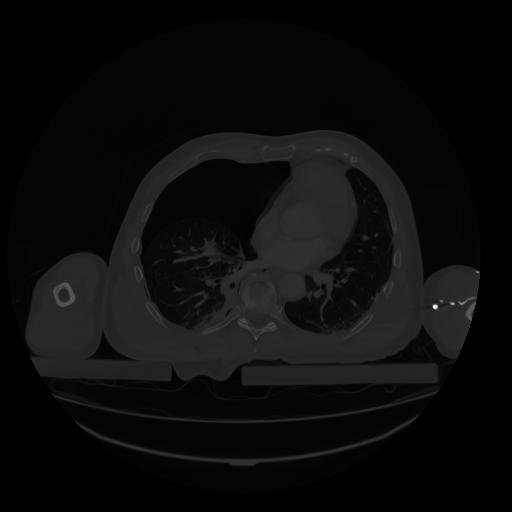

28 CUERPO,CE,Vol,2.0,CUERPO,,